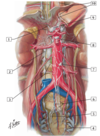

1 - abdominal aorta

2 - celiac trunk

3 - left hepatic artery

4 - cystic artery

5 - hepatic artery proper

6 - right gastric artery

7 - gastroduodenal artery

9 - common hepatic artery

11 - short gastric arteries

12 - splenic artery

13 - left gastric artery